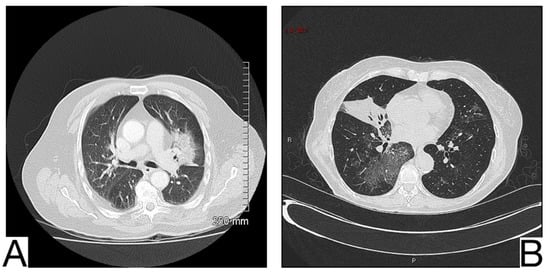

In addition to anamnesis, radiological features (Figure 7A,B) for differential diagnosis are the possible coexistence of ground-glass opacities, pavement, and consolidations with different times of occurrence about COVID-19 pneumonia []; the pattern of crazy pavement—diffuse, bilateral, with central disposition—and ground-glass opacities with subpleural preservation. Condensations are late and generally coexist with pleural effusions; bilateral pleural effusions, more evident in the alveolar phase of edema []; mediastinal lymphadenopathy; cardiomegaly.

Figure 7. Acute pulmonary edema (A). Ground glass opacity in mainly perihilar and dependent distribution (B). Bilateral airspace opacification in central peribronchovascular distribution and smooth interlobular septal thickening (indicating interstitial edema) and moderate bilateral pleural effusion. Note. Case courtesy of The Radswiki, Radiopaedia.org, rID: 1183 (A) and Dr. Rania Adel Anan, Radiopaedia.org, rID: 95825 (B).

The distribution of lesions on chest x-ray and CT is different, with the predominance of central lesions in the AHF compared to patients diagnosed with COVID-19 pneumonia [,,].

Pleural effusion and cardiomegaly, mediastinal lymphadenopathy, septal thickening, and dilation of pulmonary veins are found in a significantly higher percentage of patients with AHF.

The distribution of lesions on chest CT, pleural effusion, and cardiomegaly can provide important information to clinicians in evaluating the differential diagnosis [,,].